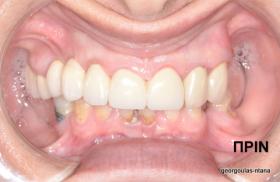

Στην ασθενή αυτή πραγματοποιήθηκε ανοικτή ανύψωση ιγμορείου άνω αριστερά. Σε πρώτη φάση πραγματοποιήθηκε η οστική αύξηση και 6 μήνες μετά τοποθετήθηκαν 3 εμφυτεύματα. Τόσο στην πανοραμική όσο και στην τομογραφία κωνικής δέσμης (CBCT) που πραγματοποιήθηκαν 6 μήνες μετά την ανύψωση είναι εμφανής ο σχηματισμός οστού. Η τελευταία ακτινογραφία και φωτογραφία λήφθηκαν 5 χρόνια μετά την προσθετική αποκατάσταση.